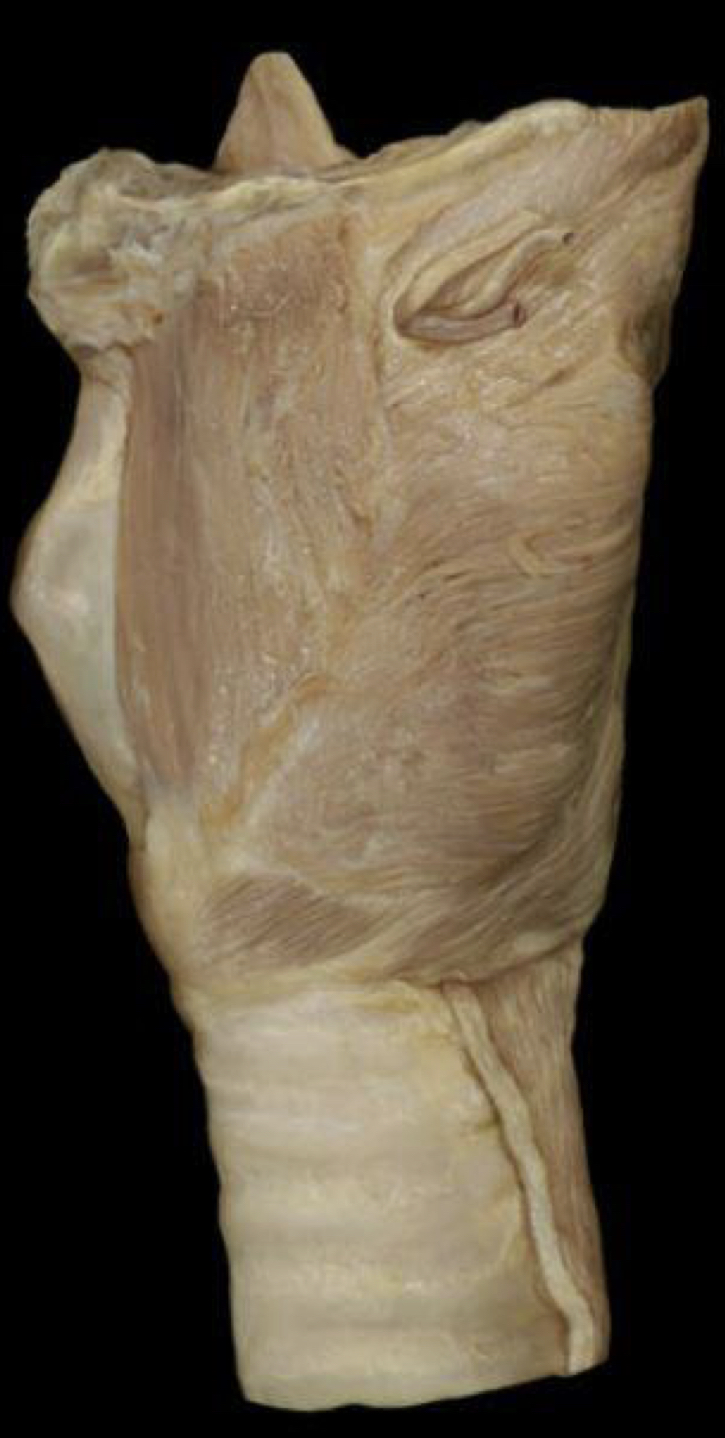

What structure is shown?

Larynx __lateral__ view